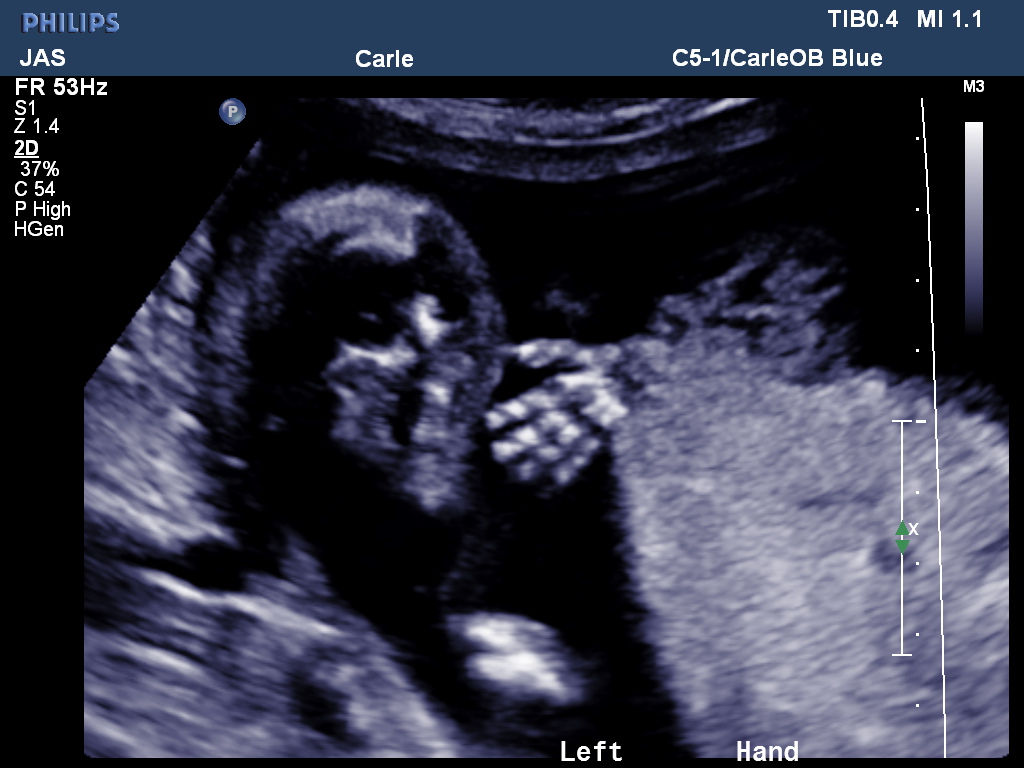

Here’s our baby girl: